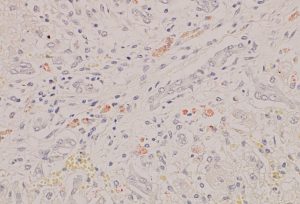

死亡した子牛の眼を見ると、明らかな黄疸で(写真2)、死後解剖では肝臓に銅の沈着(ロダニン染色という方法で調べます)が見つかります(写真3)。

写真3 ロダニン染色肝臓